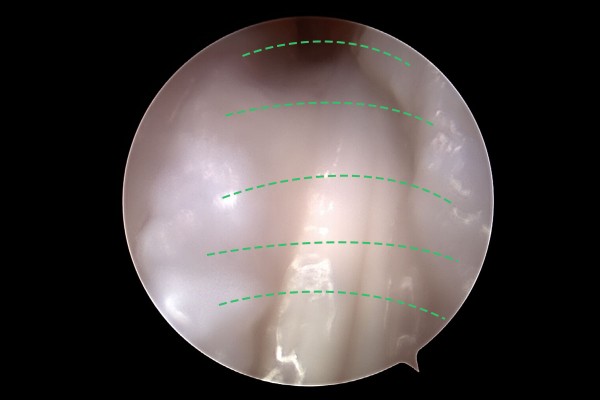

내시경 화면을 보시면 힘줄을 덮고 있는 힘줄막이 확인되고, 이 힘줄막에 힘줄의 입구를 터주고,

e2dae621a1572a5ea8be78c4dc6d0de9_1768292753_1959.jpg

수술 도구를 이용하여 힘줄을 둘러싼 두꺼운 막을 절제하여, 좌/우 힘줄덮개로 나눠주면 힘줄에 가해지는 압박이 줄어들게 됩니다.